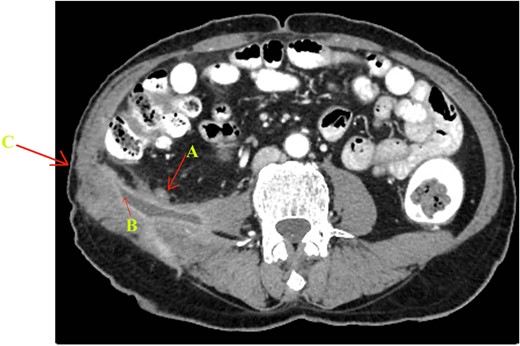

The culture of the discharge demonstrated mixed bacilli. The fluid was negative for AFB and fungus on staining. A multi-detector computed tomography (MDCT) abdomen with multi-planner reformation (MPR) images revealed a chronic inflamed thick-walled appendix tip leading to a high-density fluid collection over right psoas muscle in retroperitonium, which was then seen communicating exteriorly with a fistulous tract. There was no intraperitoneal collection noticed (Fig. 2).

MDCT abdomen with thin axial post-contrast image showing (A) appendix tip opening in (B) psoas abscess cavity leading to (C) fistulous tract opening externaly in right lumbar region.